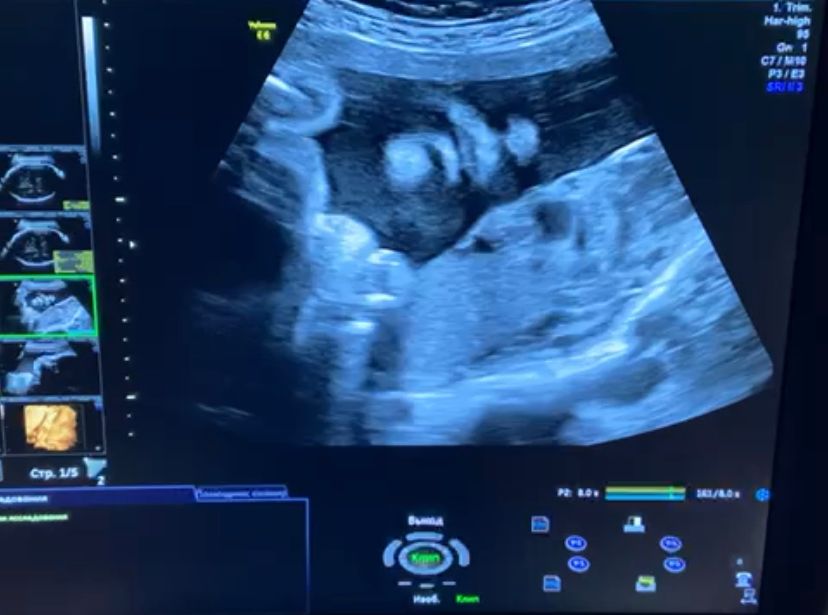

Сегодня была на УЗИ, малыш чудесный просто)) весит 1500, маленький, говорят, но в табличные нормы укладывается)) Записали мне видео, где язык показывает 😅 Вообще на всех УЗИ то руки сосет, то жует что-то... очень мило и забавно)

Показали профиль и анфас. Такие губешки там сладенькие и носатенький)))

Еще стало ясно, почему дышать так тяжело, малыш тусит в животике вытянувшись, пяточки в ребрах, все мне зажал 🙈